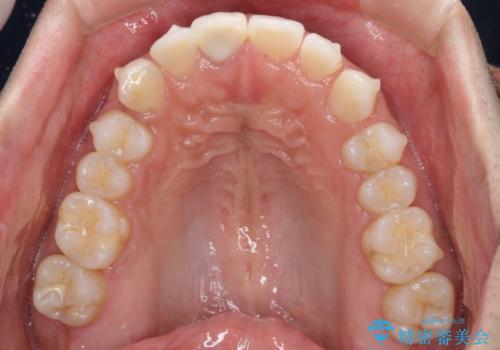

口が閉じにくい インビザラインによる矯正治療

- 口の閉じにくさを気にして来院された患者様です。

患者様と相談の上、横顔の印象から抜歯矯正は必要ないと判断し、IPR(歯と歯の間)並びに歯列全体の後方移動により口元の突出感の改善することとしました。

しっかりと装着時間を守り、ゴムかけも徹底していただいたので、思いの外口元を引っ込めることができました。

これ以上の改善を望まれましたが、非抜歯矯正でこれ以上口元を引っ込めると食いしばりすやすい咬合となるため、この歯列で終了としました。